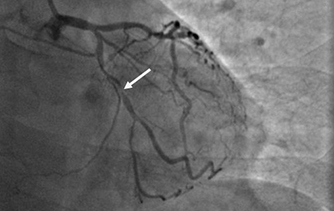

近日,河北醫(yī)科大學附屬燕達醫(yī)院心血管內(nèi)三科成功完成一例非常特殊的手術——冠心病三支病變微創(chuàng)介入完全血運重建術?;颊呃钕壬谛牟〔∽儤O其嚴重,全部三支主干動脈均重度狹窄,各處求診均被告知無法微創(chuàng)介入手術,只能開胸搭橋。拒絕開胸的李先生慕燕達醫(yī)院心血管內(nèi)三科北京安貞醫(yī)院專家團隊之名,就診于燕達醫(yī)院,由翟光耀主任為其行 “一站式”手術,一 次 性完成三支動脈的修復!手術非常成功,李先生術后恢復良好,滿意出院。   震驚 患者三支血管均90-99%狹窄 ..